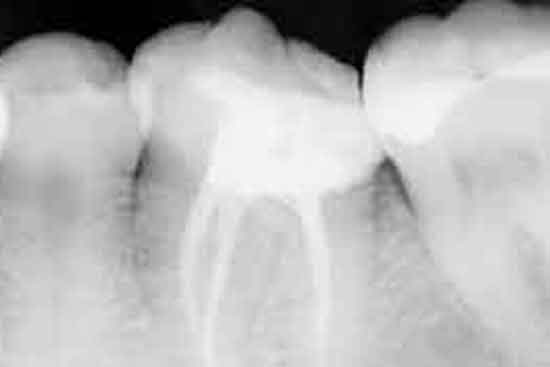

Los dientes poseen en su interior una cámara donde se encuentra la pulpa, el nervio, éste discurre por las raíces hasta llegar al hueso. Puede verse afectado por múltiples factores como son caries, lesiones periodontales, fracturas, etc, que producirán inflamación pulpar, cuando esta es irreversible, el nervio se necrosa causando problemas como dolor, flemón, y muchas veces dan como resultado infección. Para que esta infección no tenga lugar, o incluso para tratarla una vez haya aparecido, el tratamiento indicado es una endodoncia.

La endodoncia consiste en la remoción del tejido pulpar del interior de la cámara y los conductos de las raíces dentales. Para ello utilizamos una serie de limas, mediante un sistema rotatorio, de diferentes diámetros ensanchando los conductos y otorgándoles cierta conicidad para, posteriormente, rellenarlos y que queden sellados no permitiendo el paso de bacterias desde la boca al hueso y los tejidos que lo rodean.